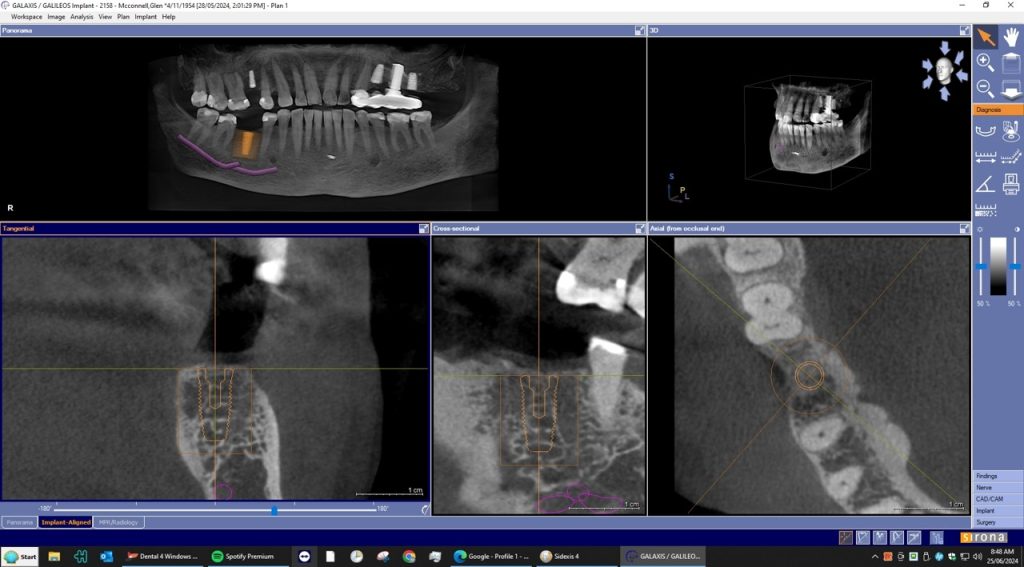

A dental Implant is a titanium “root” that integrates directly with the surrounding bone and replaces the function of the natural tooth. Neoss Implants are made using the best quality medical grade titanium, which is well known for its proven biocompatibility, and have a treated surface to facilitate bone integration.